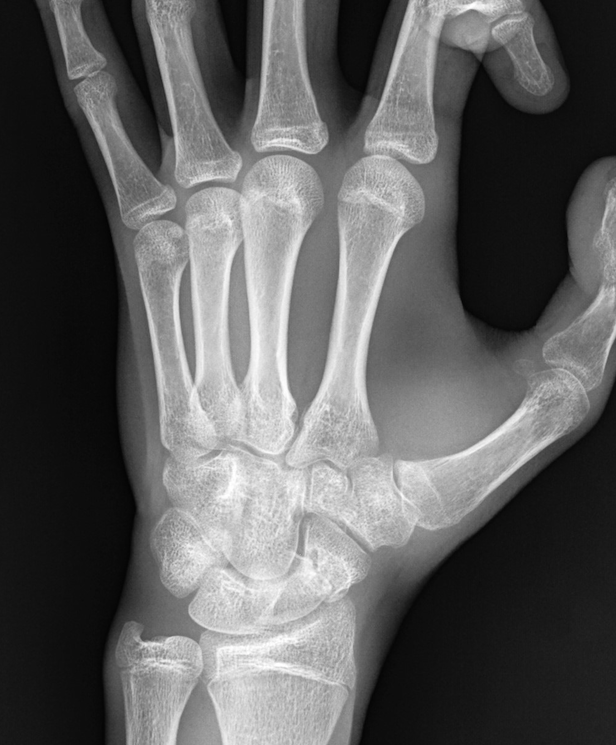

• Chirurgia della Mano e del Polso

La chirurgia della mano è una superspecializzazione che tratta patologie malformative, de...